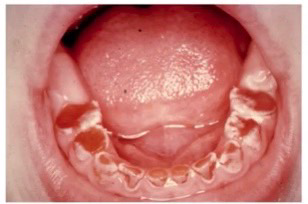

Dentinogenesis imperfecta(DI)